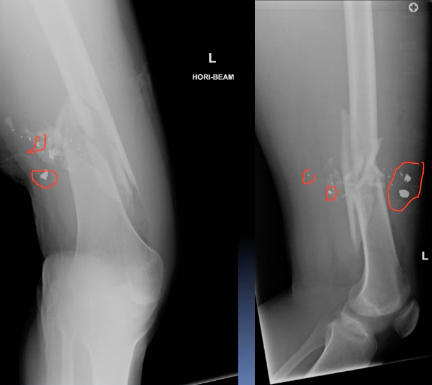

A 30 year old man presented to the ED with left knee pain after a cycling accident.

On examination there was no deformity, but it was painful for him to weight-bear. Movements of his knee were painful, and this limited his movements.

What is a lipohemarthrosis?

Results from an intra-articular fracture with escape of fat and blood from the bone marrow into the joint, and is most frequently seen in the knee.

What normal variant can be seen in this image?